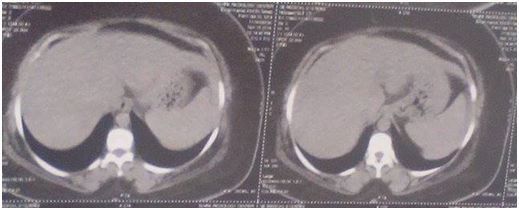

Thirty-three patients of MTNBC presented in a period from February 2013 to March 2015 were treated with gemcitabine\carboplatin. Patients had a median age of 43.6years (range, 24-71 years, S.D: 11.161)23 patients were premenopausal (69.7%) & 10 patients were postmenopausal (30.3%). Approximately 81% of patients had a good PS (0-1). 12 patients were basal subtype (positive ck5/6) from twenty patients who had accessible specimens for examination of cytokeratin (12out of 20=60%), Mean overall survival (OS) in patients has basal subtype were 12 months, while in patients has non-basal subtype were 12.96 months (95% CI-3.53-5.45) P <0.242). Median progression-free survival (PFS) in basal subtype were 5.857 months while in non-basal subtype were 6.15 months (95% CI-1.79738-2.39079) P <0.456).patient had complete response (CR) Figure 1.

Figure 1 Liver metastasis, a. Before treatment & b. After treatment.